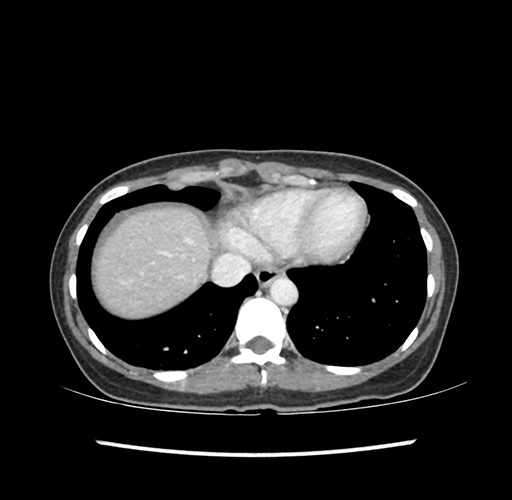

Imaging Analysis

Look through the patient's CT scan to identify any areas of concern for the necessary procedure.

Based on your CT findings, which issue(s) would give reason for "planned slowing down moment(s)" in this case?

Considering a standard left lateral sectionectomy procedure, what step(s) of the operation would you do differently in this case ?